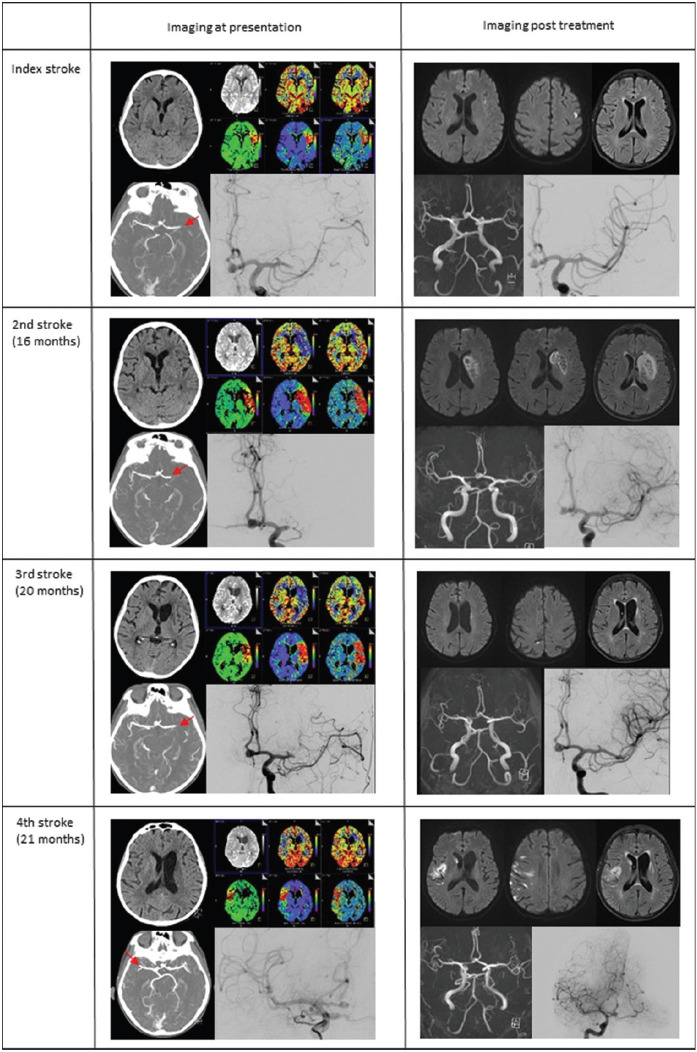

Antiphospholipid syndrome (APS) is known as a rare etiology of embolic ischemic stroke. In individuals below 50 years, up to 20% of strokes are associated with APS, whereas in patients >50 years, it is considered a very seldom cause of stroke. We describe the course of a 66-year-old white woman, who experienced four embolic strokes with large vessel occlusion over a period of 2 years, which were repeatedly and successfully treated by mechanical thrombectomy. Initially attributed to atrial fibrillation and treated with direct oral anticoagulants, the patient was finally diagnosed with primary APS due to isolated anti-beta 2-glycoprotein antibodies and successfully treated after several stroke recurrences. After initiation of Vitamin K antagonist therapy, no further strokes occurred. For recurrent embolic stroke despite oral anticoagulation, late-onset APS might be considered a rare etiology also in the elderly.